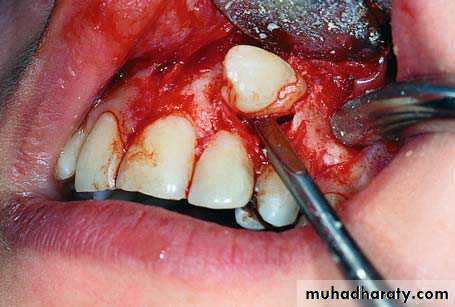

Clinical photograph of the labial area where the right canine is localized labially

right canineSurgical procedure for removal of right impacted canine. A trapezoidal incision is created buccally. It is desirable to make an intersulcular incision extending to at least one to two teeth in each direction from the area of interest

Reflection of the mucoperiosteal flap